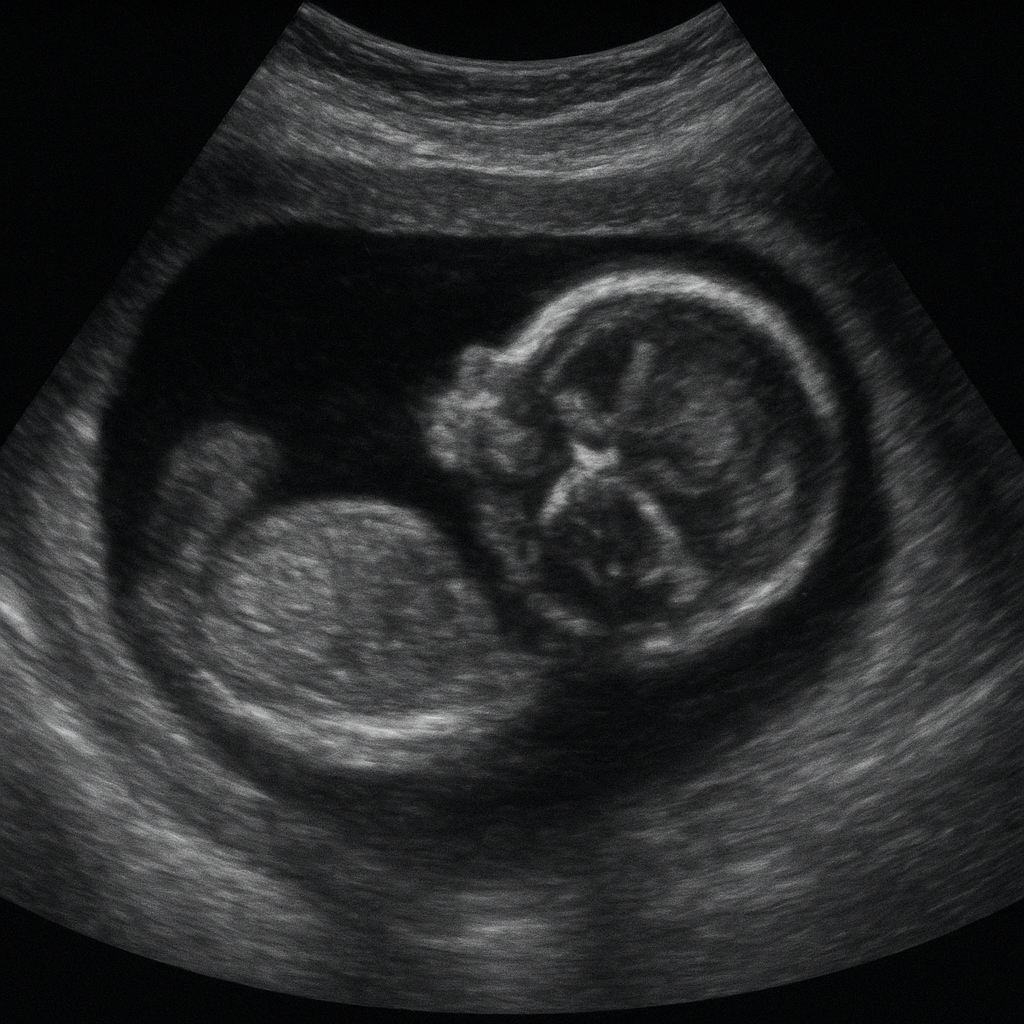

Badanie USG serca płodu stanowi kluczowy element diagnostyka prenatalnej, który pozwala na ocenę stanu anatomicznego i funkcjonalnego narządu odpowiadającego za krążenie krwi u rozwijającego się dziecka. Dzięki zaawansowanym technologiom obrazowanie staje się coraz bardziej precyzyjne, a lekarze mogą wykrywać nawet drobne patologiczne zmiany we wczesnym etapie ciąży. W poniższym artykule przybliżymy znaczenie badania, jego przebieg, wykrywane wady oraz zalecenia przed i po wykonaniu badania.

Dzięki dostępności nowoczesnych aparatów USG z wysoką rozdzielczością można już w II trymestrze przeprowadzić szczegółowe badanie serca płodu. Wykrycie patologii w odpowiednim momencie umożliwia wdrożenie zindywidualizowanego planu postępowania oraz minimalizuje ryzyko zagrożeń dla matki i dziecka.

Badanie ultrasonograficzne serca płodu dzieli się zasadniczo na dwa etapy:

• USG podstawowe – ocena morfologii serca, jam serca, zastawek i głównych naczyń krwionośnych.

• Echokardiografia zaawansowana – badanie dopplerowskie przepływów krwi, analiza funkcji skurczowo-rozkurczowej mięśnia sercowego.

Wysokiej klasy aparaty oferują także możliwość rejestracji obrazu w formacie 3D/4D, co pozwala dokładnie zobrazować nie tylko anatomię, ale również ruch zastawek i ścian komór.